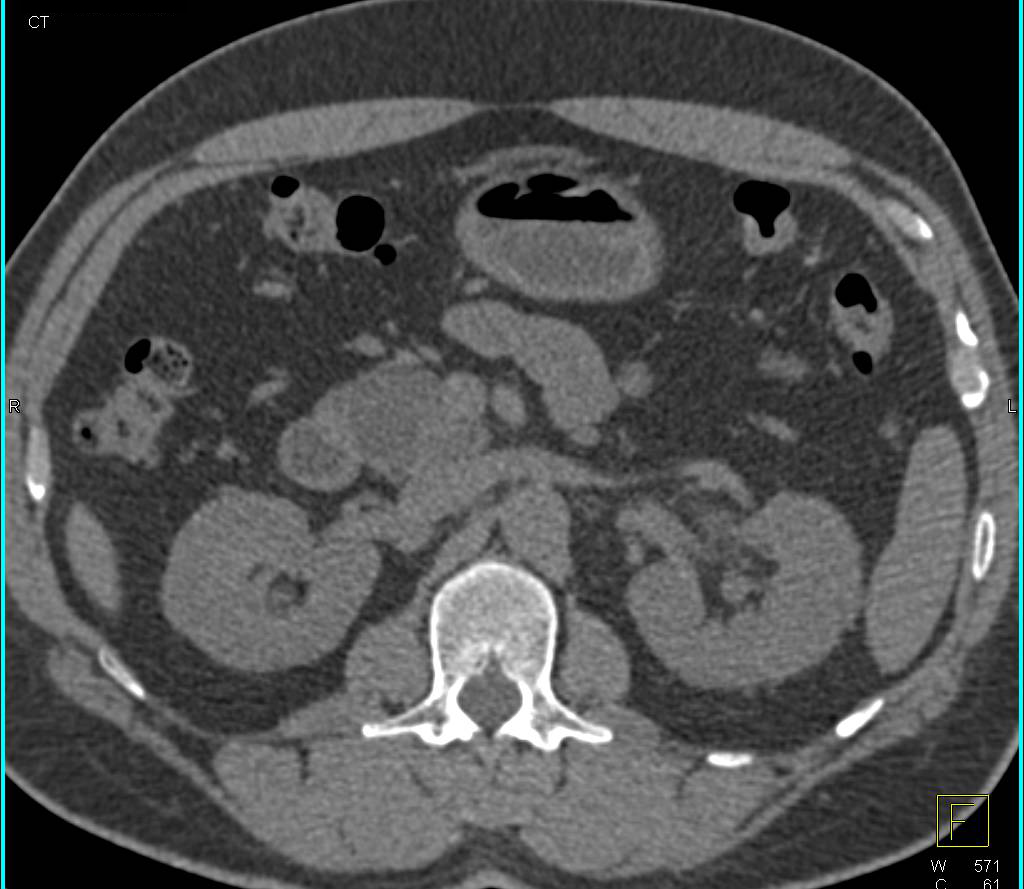

Pancreatic Cancer Obstructs the Common Bile Duct and Encases the Superior Mesenteric Vein (SMV)